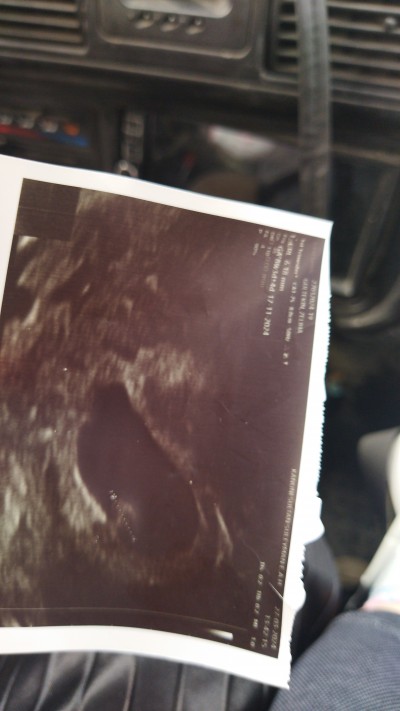

Kızlar geçecekten merak ediyorum 6 haftalık Beta HCG 37854 çıktı doktor ikiz olabilir dedi ama bir Bebek ve kalp atışı vardı diğeri için ümit. Vermedi ilerleyen zamanlarda belli olur dedi burda kaç kese var yada Beta değeri yüksek mi sizce ikiz ihtimali büyük mü

image

6 haftalıkken benim, 59bindi, doktorum hiç ikiz demedi, doktorunuzun sadece beta değerine bakarak ikiz demesine de çok şaşırdım çünkü usg kağıdınız da bariz tek gebelik var şuan için (ikiz gebelik durumunda 8. Haftadan sonra da belli olabiliyor), beta değeri ile sadece ikiz demek çok yanlış olur, beta ve usgnin beraber değerlendirilmesi lazım. Benim sizinle aynı hafta da 59bindi hatta, sizden çok daha yüksekti ama tek gebelik. Vücudumuzun ürettiği hormonlarla da alakalı biraz.